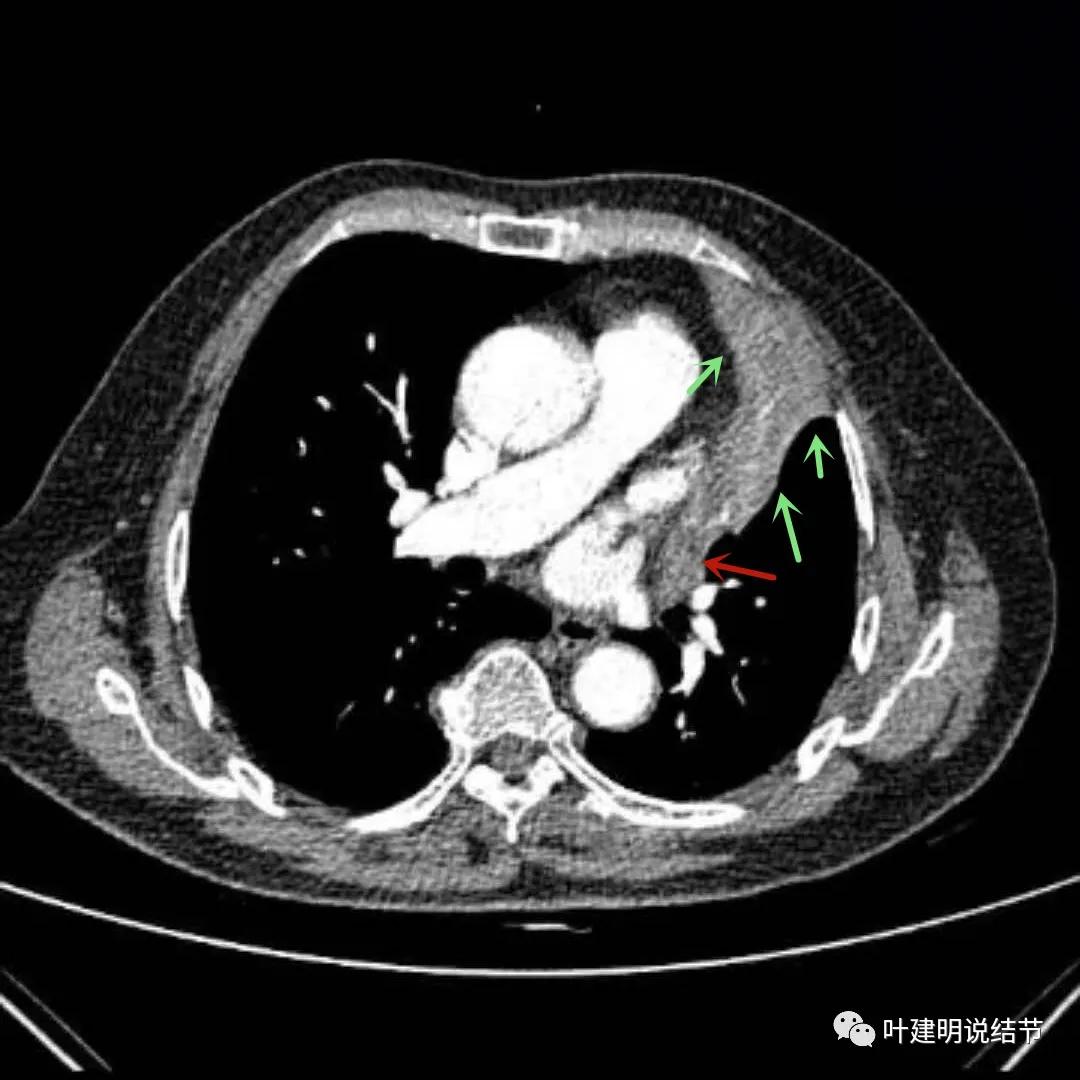

上图绿色箭头所指区域考虑不张的肺组织,红色箭头所指附近为肿瘤,且有膨胀性

上图绿色箭头所指区域考虑为肺不张,红色示肿瘤处,桔色箭头所指处是被肿瘤包绕的肺动脉分支